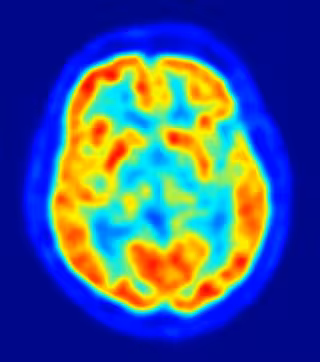

Investigadores de la Universidad de Stanford en Estados Unidos han descubierto un circuito neural que controla la ansiedad. El estudio, realizado en ratones, utiliza proteínas sensibles a la luz para controlar la actividad neuronal e indica que la ansiedad está continuamente regulada por mecanismos opuestos que se contrabalancean dentro de una región cerebral llamada amígdala. El trabajo se publica esta semana en la edición digital de la revista 'Nature'.

Se cree que la amígdala participa en el procesamiento emocional y la ansiedad generalizada, pero ha sido difícil identificar las subregiones y conexiones críticas. El estudio muestra una red compleja de células y conexiones específicas que influyen en la ansiedad y demuestra el potencial de esta técnica, la optogenética, para desvelar los circuitos neuronales complejos que subyacen a la enfermedad psiquiátrica.